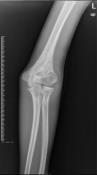

儿童陈旧性孟氏骨折

术后肘关节侧位片

儿童陈旧性孟氏骨折,术前桡骨小头陈旧性脱位,经截骨矫形治疗后1个月,桡骨小头已复位,患儿肘关节屈伸功能(1-2图),前臂旋转功能(3-4图)正常